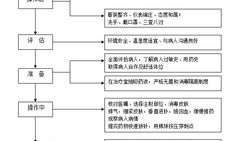

肌肉注射操作视频,步骤与技巧全解析

亲爱的读者们,你是否曾经好奇过,那些在医院里忙碌的医护人员是如何进行肌肉注射的?今天,就让我们一起揭开这个神秘的面纱,通过一段特...